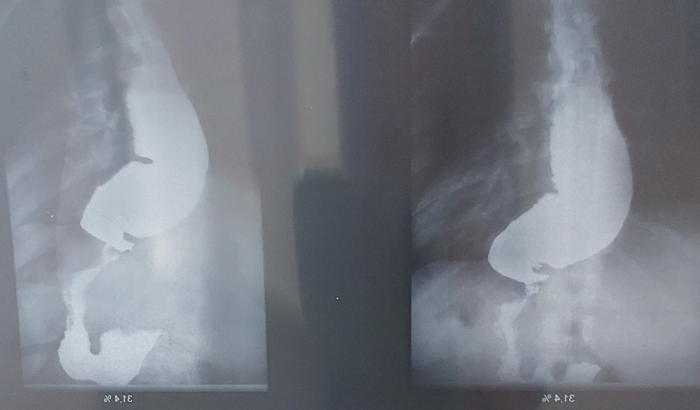

Eu Rozelandia 41 anos residente no itaim paulista/SP em 2013 fui diagnosticada com Acalasia mega esôfago e uma doença que causa ausência dos movimento que empurram os alimentos para o estômago e assim causa a dificuldade para engolir sólidos e liquidos .A doença causa vômitos (com alto risco de broncoaspiraçao ),vomito tdo que tento comer ate água. Os sintomas estão se agravando cada vez mais ,se nao fizer a cirurgia urgente ,corro o risco de ter que retira o esôfago. A cirurgia é realizada na cidade de João Pessoa ,pelo Dr. ANTÔNIO CARLOS CONRADO(endoscopista).